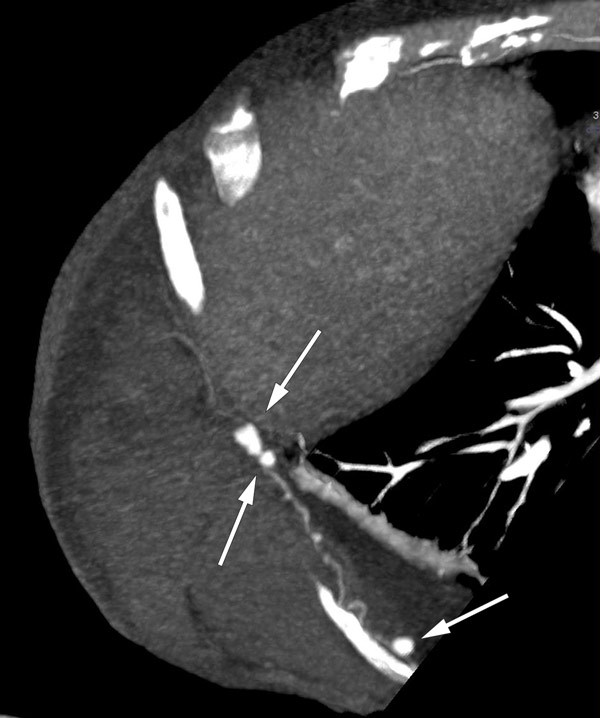

I rekonvalesensperioden etter den andre tarmoperasjonen fikk kvinnen på nytt en stor blødning, denne gang fra den høyre nyren. På CT-arteriografi fant man blødning subkapsulært, inferiort mot høyre fossa iliaca og høyre flanke. Hun ble tilsett av urolog, som konkluderte med konservativ behandling i form av blodtransfusjon.

Som regel blir diagnosen stilt ut fra biopsi med funn av transmural nekrotiserende inflammasjon i mellomstore arterier. Alternativet til biopsi er typiske angiografifunn av multiple aneurismer og stenoser. CT- og MR-undersøkelse har i stor grad erstattet konvensjonell angiografi, og CT thorax/abdomen av vår pasient viste multiple karaneurismer og pseudoaneurismer i tarmkrøs, rundt ventrikkel, i lever, nyrer og interkostalarterier. Hun fikk standard behandling for tilstanden med steroider og cyklofosfamid,

Utredning av vaskulitter kan være utfordrende – både med tanke på differensialdiagnoser og endelig typebestemmelse av dem. Vi har beskrevet en pasient med kjent nevrofibromatose som ble behandlet for vaskulitt. Utredningen tok tid, og pasienten hadde flere alvorlige blødninger, med behov for transfusjon og kirurgiske inngrep, før diagnosen ble satt. Allmenntilstanden ble gradvis svekket inntil hun var helt sengeliggende. CT-undersøkelse avdekket multiple aneurismer, og hun blødde fra tre av disse, beliggende i mesenteriet, interkostalarterier og nyrearterier.